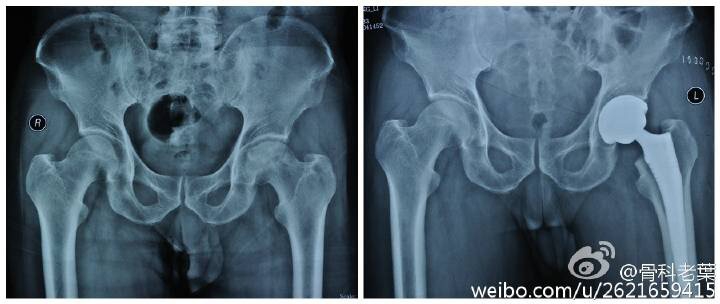

另附典型病例若干: